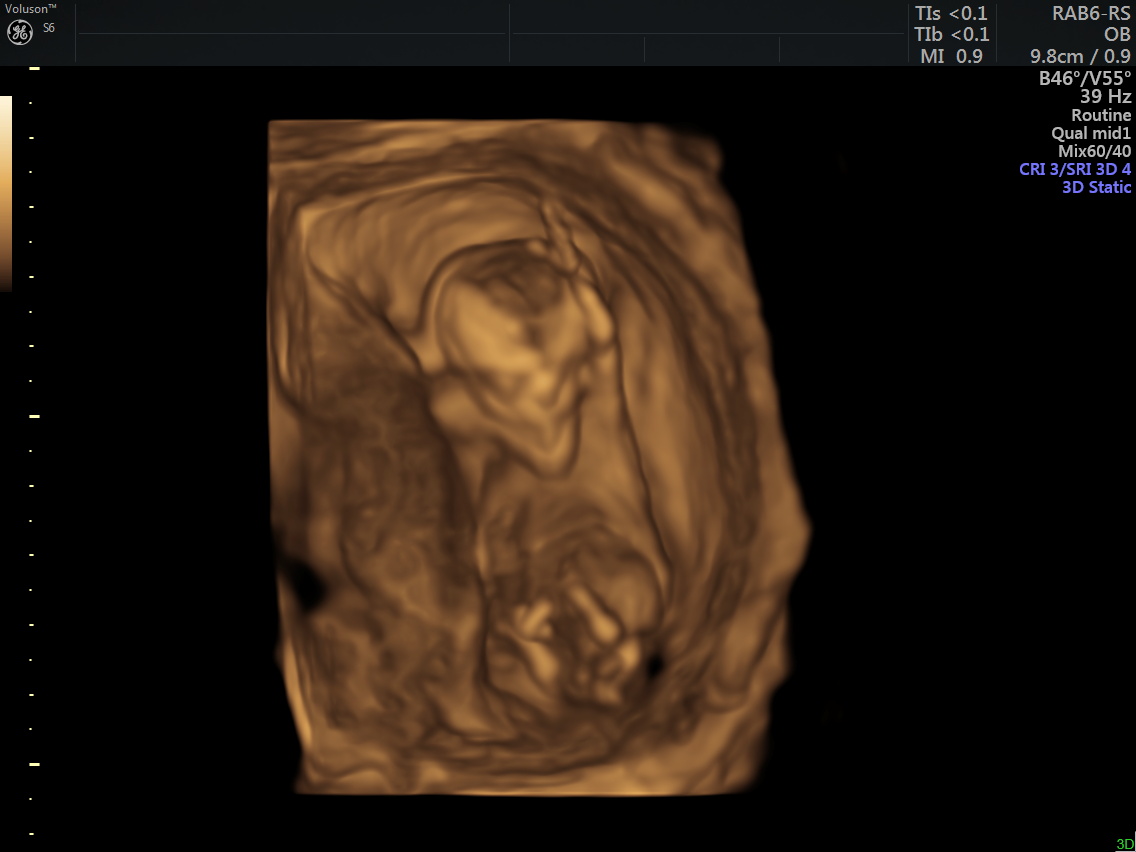

Merhaba, bizim cinsiyet hala kesinleşmedi 🙂 ben biraz nubu araştırdım. Ve size ilk gönderdiğim resimde nub kısmının dik olduğunu gördüm. Ama aynı anda verilen diğer görüntü aşağıda fakat burda da nubu paralel gözüküyor. Kafam karıştı açıkcası. Hangisi sizce?

Emin olmamakla birlikte kız gibi görünüyor canım umarım sağlıklı kucağına alırsın sonucu kesin öğrendiğinde de yazarsan sevinirim :hamis: :d040: